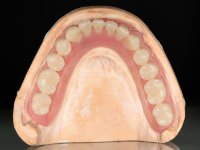

Two dental implants were planned in the CBCT scan, in the area of the inferior canines. The dental extractions were performed and, simultaneously, the alveolar crest was flattened and the implants were placed. Three issues were considered while implant placement: parallelism of the axis, same height of the implant’s neck, and same position in the coronal plan. This 3D insertion is essential to have a good retention of the overdenture in the future. Patient’s removable denture was fixed in the dental lab, to include the extracted teeth, and a soft-tissue relining was done over the healing abutments. After the osseo-integration period, a first impression was done with an open-tray and a doble-mix technique. This dental impression allowed the production of screwed wax-rims and an individual tray for a functional impression. A second impression, final, was done with an individual tray with a monophasic silicone. The occlusal wax-rims were correct in the mouth according to the full denture guidelines. Special care was taken with the occlusal vertical dimension and the support in the soft-tissues. A silicone bite registration material was used to better defined the intermaxillary relations. Teeth set-up was done in the dental lab with the selected tooth color. Due to the fact that the base was screwed to the dental implants, the teeth set-up was functionally evaluated in the mouth. Another silicone bite registration material was used to allow final occlusal adjustments. Finally, the locators were screwed and the retention nylons were selected according to the patient needs.